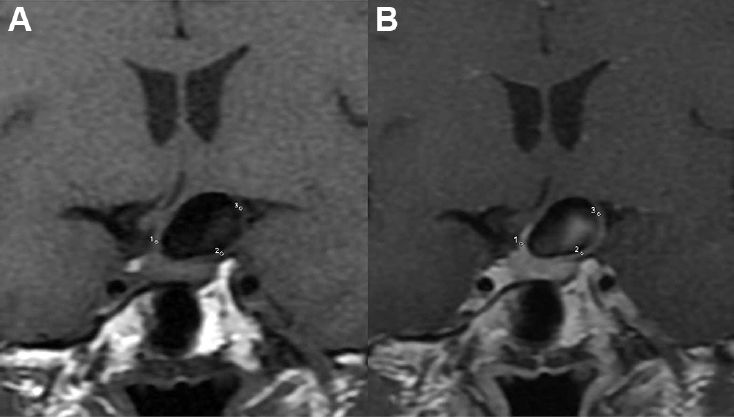

MR使用GE3.0T机器,8通道头部线圈。检查方案包括3D TOF MRA,增强前/后的T1WI HRMRI。所有图像由2名经验丰富的放射科医师在GE工作站上分析。CTA重建后,最佳角度测量动脉瘤的瘤颈、深度、宽度,动脉瘤与载瘤动脉的夹角,部位,是否双分叉,形态。动脉瘤的位置分为前循环和后循环。MRI分析,分析者定义增强模式,增强程度,以及瘤壁厚度。与增强前扫描相比,瘤壁增强模式分为无增强,全部增强(全部瘤壁增强),部分瘤壁增强。在PACS系统上3倍放大增强前后的图像上,手动测量瘤颈部、瘤体部、瘤顶的信号强度。增强程度的计算:增强程度=(增强后最大信号强度-增强前信号强度)/增强前信号强度x100%。不同部位的瘤壁厚度在增强后图像上手动测量。统计分析时使用平均值。(图1-4)

图4.在增强前(A)后(B)的图像上,分别测量瘤颈部、瘤体部、瘤顶部的信号强度。使用瘤壁兴趣区环形区域的信号平均值。